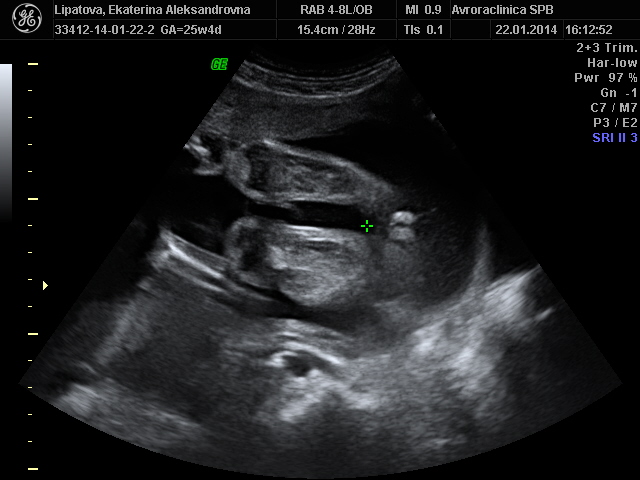

я уже ничего не вижу, поэтому прикладываю вам фото интимного характера:) девушки, у меня точно дочка?)))

У нас точь-в-точь такая фотка)) Как обозвала это моя узистка - "кофейное зернышко")) Дочурка без сомнений. Поздравляю!